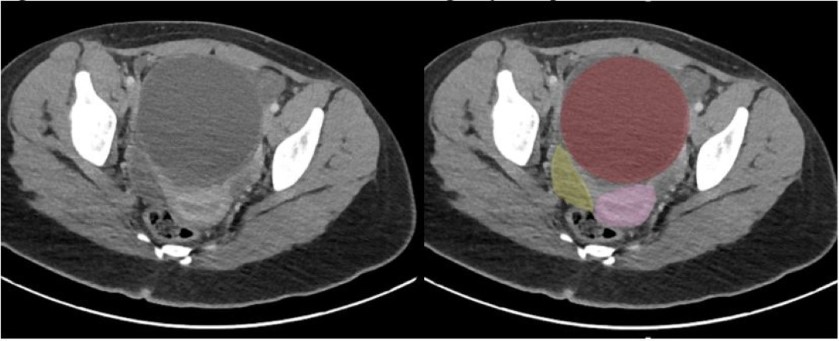

Her pain improved, and she was discharged home. She returned 24 hours later with 9/10 abdominal pain. On arrival, the patient received 4mg of morphine, 4mg of Zofran, and 1L of normal saline. Due to her persistent severe pain, she had an abdominal CT that was notable for a 10cm cystic lesion adjacent to the bladder and uterus (Figure 2). The radiologist noted the bladder was decompressed by the cyst. She was taken to the OR with gynecology and found to have a very large, edematous, and hemorrhagic right fallopian tube with hydrosalpinx. She was found to have a normal left fallopian tube and well-perfused bilateral ovaries. Her right fallopian tube was removed.

Figure 2: CT Abdomen and Pelvis. Red: Hemorrhagic Hydrosalpinx; Pink: Uterus; Yellow: Bladder